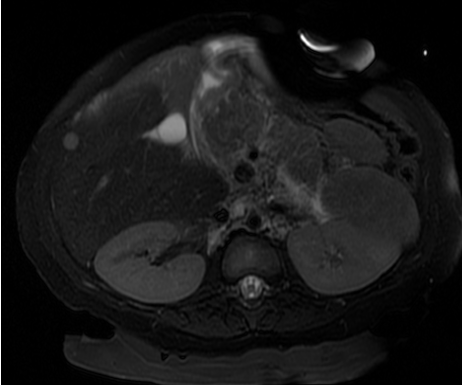

#SIOCaseSpotlight: 15-month-old with PMHx of prematurity and VACTERL was incidentally found to have a liver mass on US. AFP was 192 ng/mL (normal <8.8). MRI showed an arterially enhancing lesion in segment 6 measuring 8 mm with washout on portal venous phase.